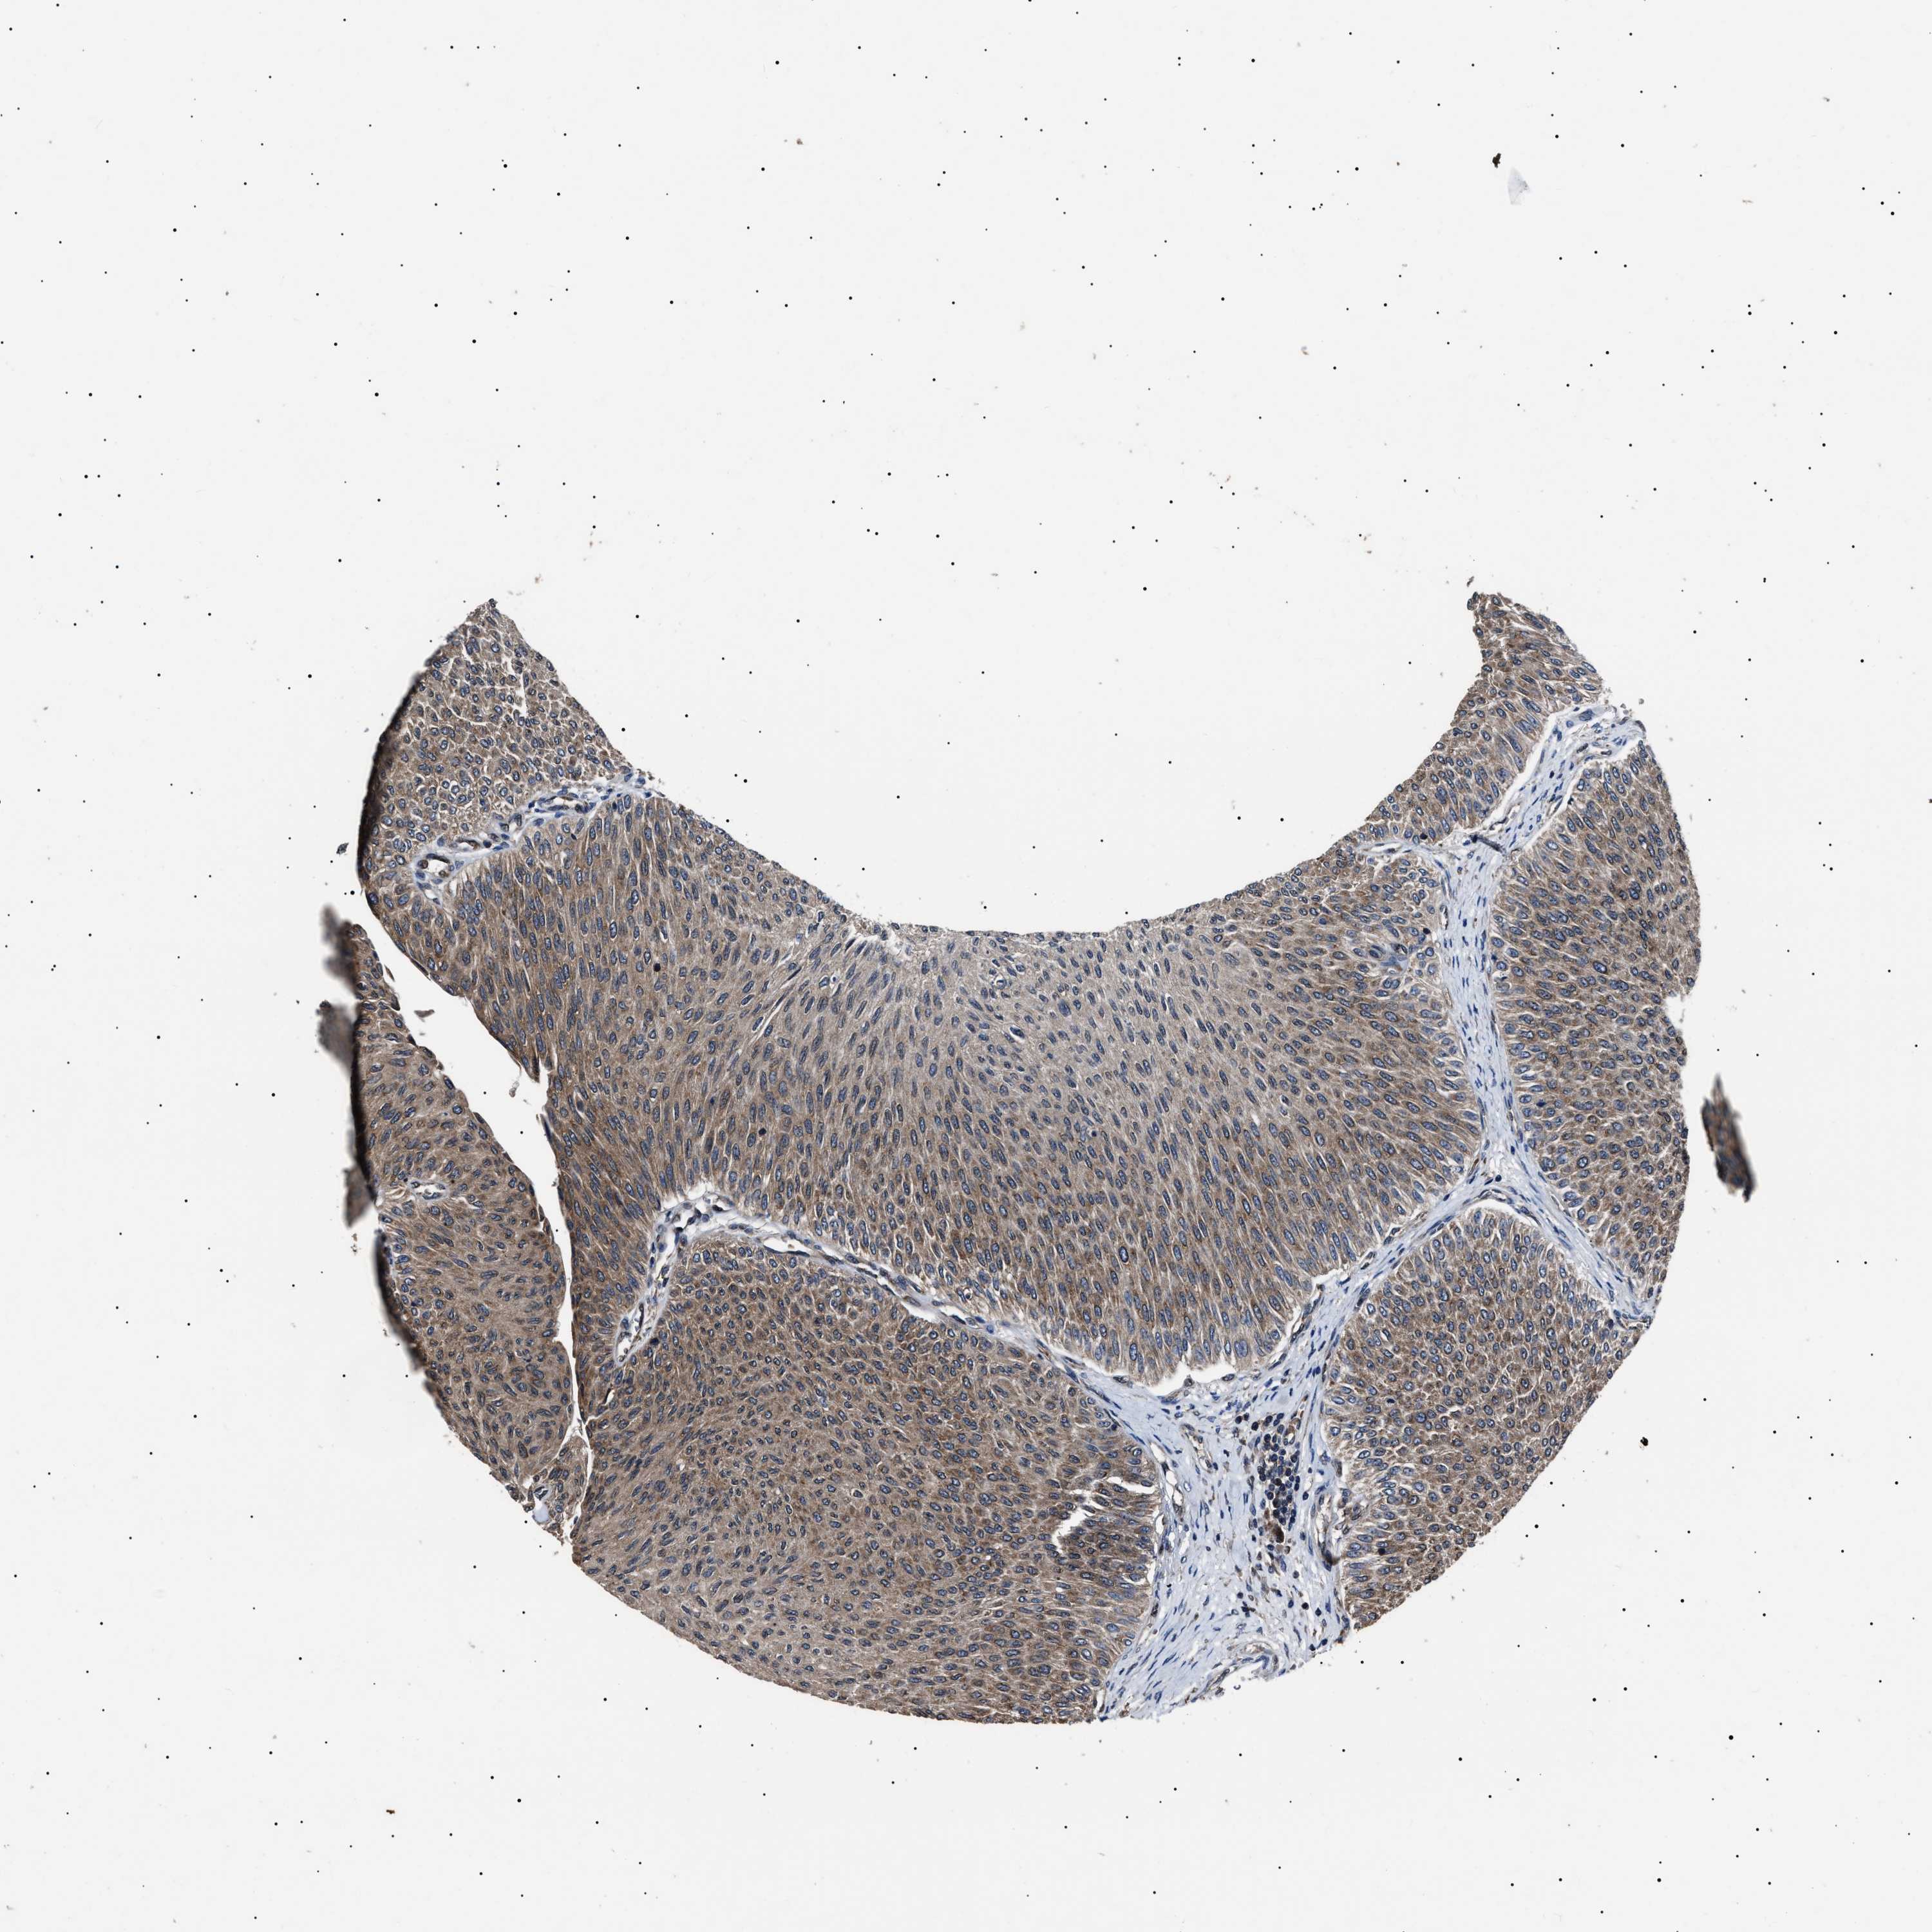

UROTHELIAL CANCER - Protein expressioni

A mouse-over function shows sample information and annotation data. Click on an image to view it in a full screen mode. Samples can be filtered based on level of antibody staining by selecting one or several of the following categories: high, medium, low and not detected. The assay and annotation is described here.

Note that samples used for immunohistochemistry by the Human Protein Atlas do not correspond to samples in the TCGA dataset.

Antibody stainingi

Antibody staining in the annotated cell types in the current human tissue is reported as not detected, low, medium, or high, based on conventional immunohistochemistry profiling in selected tissues. This score is based on the combination of the staining intensity and fraction of stained cells.

Each image is clickable and will lead to virtual microscopy that enables deeper exploration of all samples and also displays staining intensity scores, fraction scores and subcellular localization as well as patient and tissue information for each sample.

Antibody HPA018520

Antibody HPA021051

Antibody HPA029426

Urothelial carcinoma, Low grade

Urothelial carcinoma, High grade